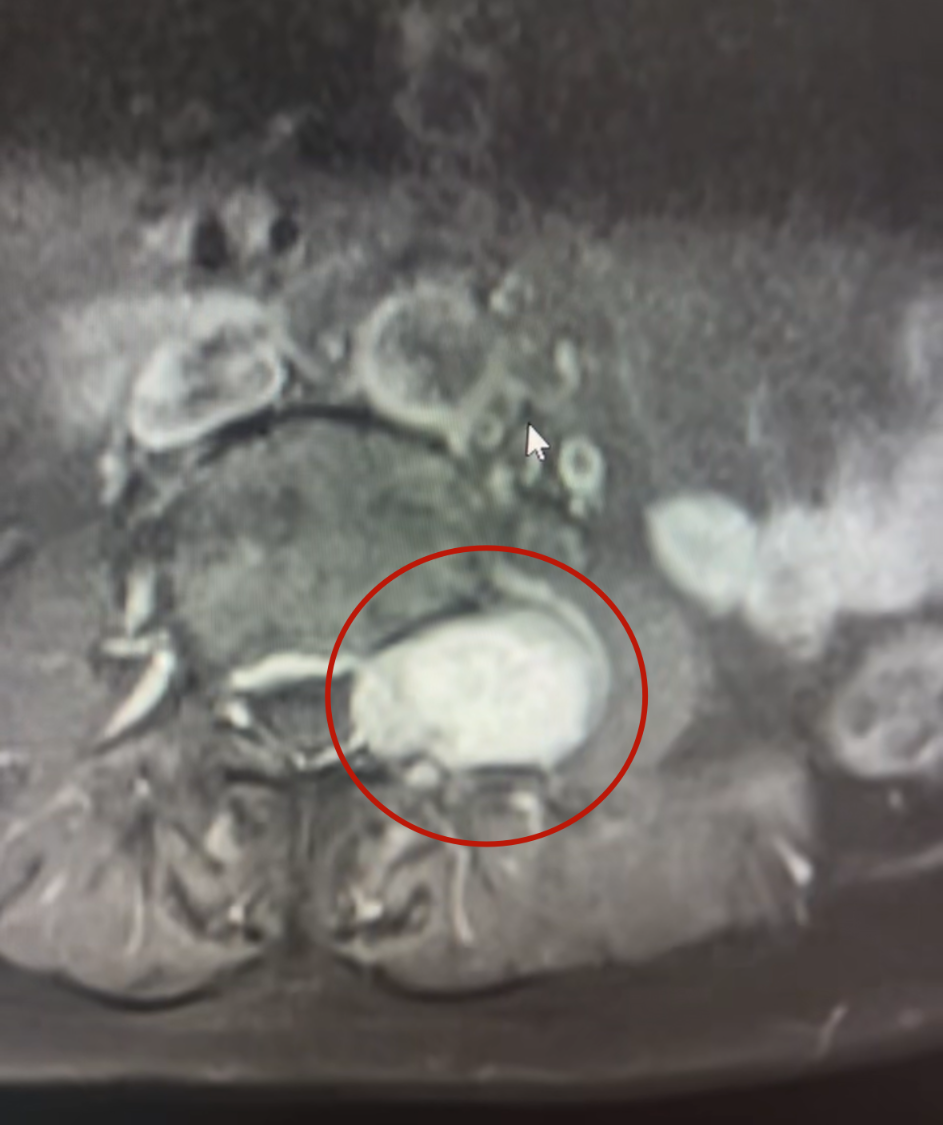

“腫瘤一半在椎管內(nèi),一半突出到椎間孔外,像啞鈴一樣卡在神經(jīng)通道上,已經(jīng)把椎骨都?jí)鹤冃瘟恕!睉?yīng)國(guó)政副主任醫(yī)師解釋道。這正是導(dǎo)致徐阿姨長(zhǎng)期左下肢麻木、無(wú)力,并出現(xiàn)嚴(yán)重漏尿,只能長(zhǎng)期使用尿不濕的根源。

▲腫瘤使錐體變形,腰大肌受壓

▲腫瘤浸入椎管,壓迫神經(jīng)